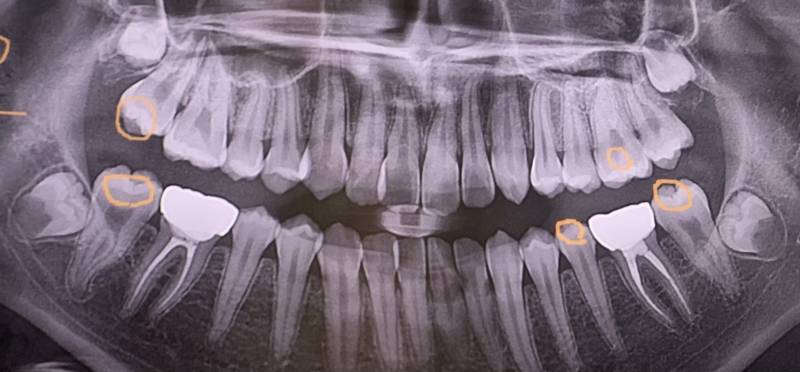

나 사랑니 어떤거같아🦷😬

맨끝에 4개 보이는 게 사랑니인데 어떤 거 같아..? 괜찮아 아니면 아플삘이야?ㅠㅠ

아픈 걸 떠나서 아래 두 개는 앞에 이가 쎀ㅂ을듯

오 어쩐지 이미 썩었더라구 이유가 머야?

나 같은 경우는! 윗사랑니는 너무 깊고 큰 영향 없어서 안뽑아도 되고 아랫사랑니는 다뽑았씀

개아픔 완전 매복이라서

바뀔가능성은 희박하고 나이 들수록 뼈끼리 유착이 심해져서 더 뽑기 어려워지니까 언눙 뽑는게 좋아 ㅠㅠ

아래는 얼른 뽑아 저거 어금니 뿌리 흡수해 안그럼 어금니도 뽑아야함

내가볼땐 사진상 말고 쓰니 입장에서 오른쪽 아래가 제일 급해보여

나는 저렇게 생긴게 뿌리가 앞인지뒤인지 누워난거였어 그래서 저런식으로 둥글둥글해보였어

그리고 나이가 난 25살이라 다 자라고도 발치하기 딱 마지노선이었어서 째서 통채로 뽑았고

근데 옆에 밀고있어서 뽑아야할거같긴하다ㅜ

위엔 방향 괜찮은데 아래는 이미 겹쳐있네